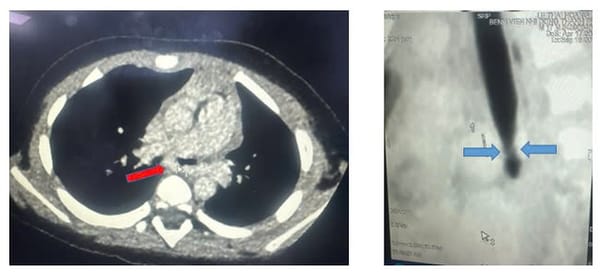

SKĐS - Viêm phổi là một bệnh truyền nhiễm, tấn công trực tiếp vào phổi và gây viêm. Đây là bệnh hô hấp nguy hiểm, đặc biệt là với trẻ sơ sinh. Việc nhận biết sớm và phát hiện mức độ nguy hiểm của bệnh để đưa trẻ đi viện